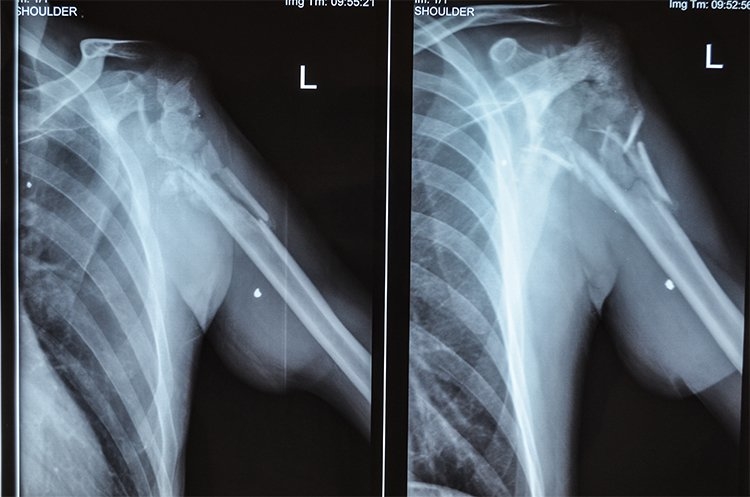

За їхніми словами, тяжку травму військовий отримав у квітні 2016 року під час бою у сумнозвісній промзоні біля Авдіївки. Олександр спіймав власним тілом гранату із АГС: поцілило просто в плече, яке повністю розтрощило. Сам чоловік дивом залишився живий.

Державні та військові лікарі пропонували Олександру лише два варіанти: або встановити штучний суглоб, що значно обмежує рухливість руки, або ж артродез, що зробить руку взагалі нерухомою. Щоб уникнути каліцтва, чоловік звернувся до лікарів проеку "Біотех-реабілітація поранених".

Днями Олександру провели основний етап лікування. Фахівці клініки ilaya імплантували у місце травми тривимірний кістковий матрикс. Крім того, зону ураження заповнили медичним гелем, насиченим власними клітинами пацієнта, що з часом мусить сформувати нову кісткову тканину.